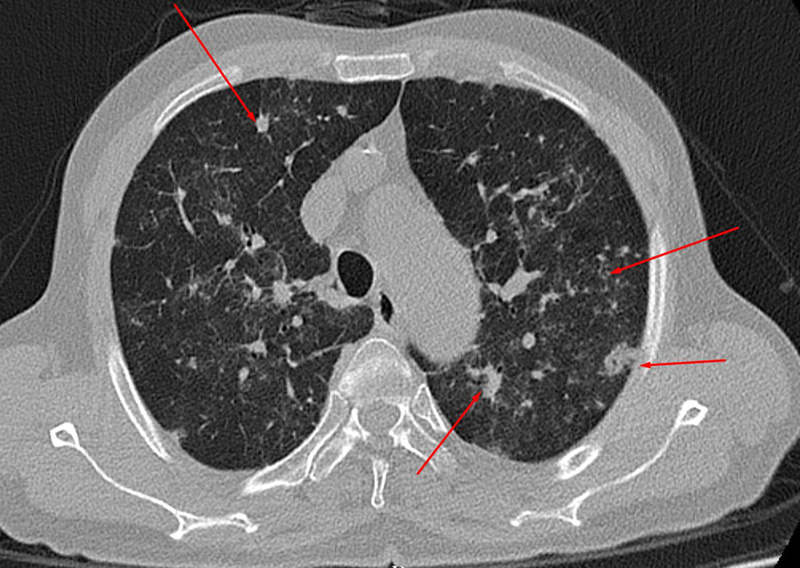

Nam bệnh nhân 65 tuổi, đến Bệnh viện đa khoa Hùng Vương (Phú Thọ) khám hậu COVID-19 do xuất hiện ho có đờm, khó thở về đêm, mệt mỏi, ăn uống kém sau 20 ngày khỏi bệnh.

Tại bệnh viện, kết quả chụp CTscaner lồng ngực cho hình ảnh phổi đông đặc, tổn thương lan tỏa hai phổi. Hiện tại, bệnh nhân đang được điều trị tại Khoa Nội.

Theo các bác sĩ, nhiều bệnh nhân mắc COVID-19 có triệu chứng nhẹ, khỏi bệnh nhanh nhưng gặp phải di chứng phổi hậu COVID-19 rất nặng nề như xẹp phổi, xơ hóa phổi, phổi đông đặc…